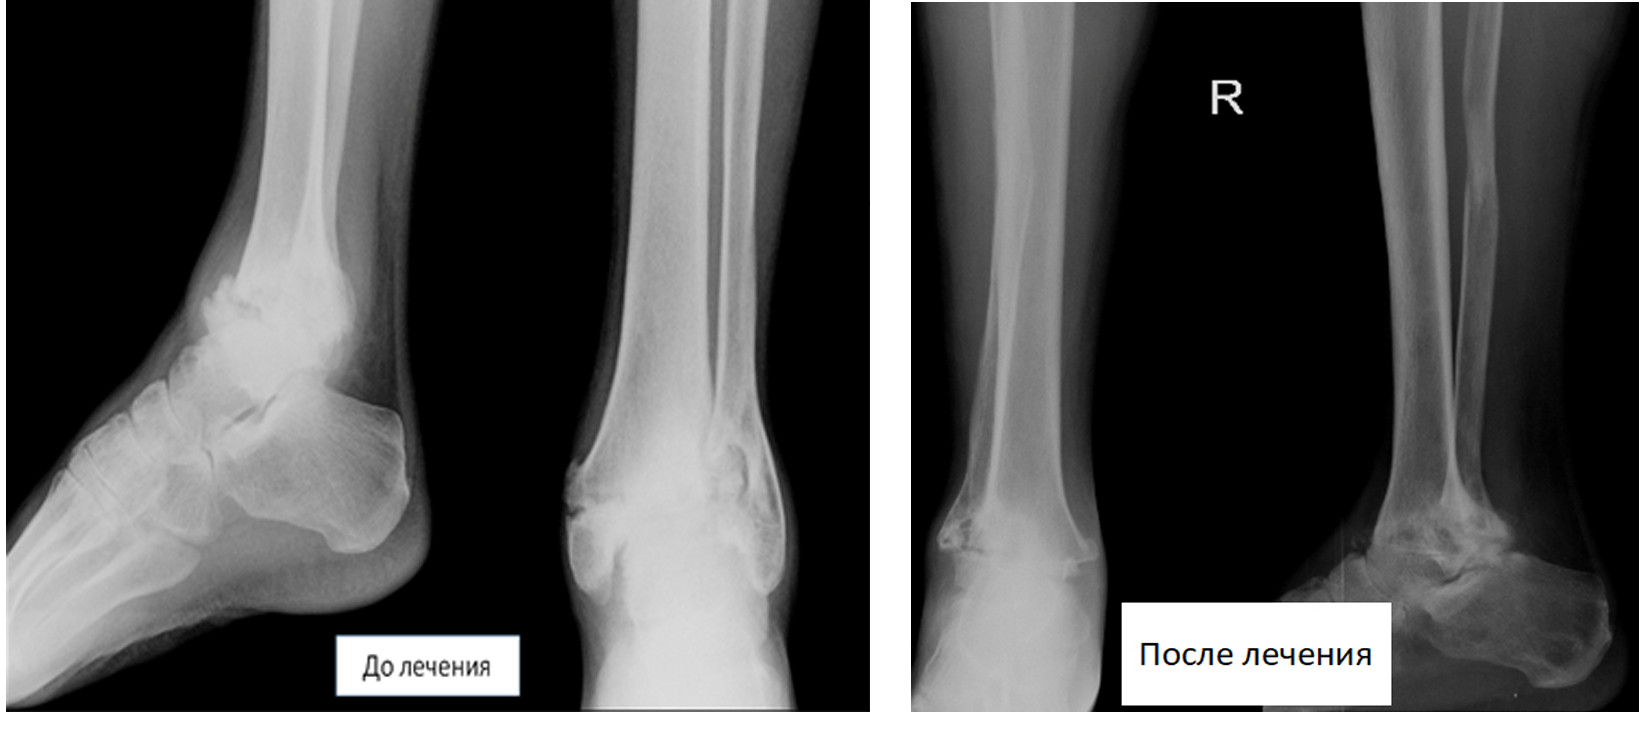

Мужчина обратился с посттравматическим артрозом правого голеностопного сустава. До обращения неоднократно лечился в различных медучреждениях, где ему проводилось медикаментозное лечение, внутрисуставное введение препаратов гиалуроновой кислоты. После каждого курса лечения в течение 3-5 месяцев боли в области сустава уменьшались, а затем вновь усиливались.

При рентгенологическом обследовании у пациента было выявлено полное разрушение голеностопного сустава. В связи с длительным неэффективным лечением и постоянными сильными болями пациенту в государственной больнице было предложено выполнить ампутацию на уровне голени.

Нами было выполнено оперативное лечение, направленное на сохранение конечности. В настоящее время пациент активно пользуется своей ногой. Ходит практически не прихрамывая и вернулся к прежней работе.